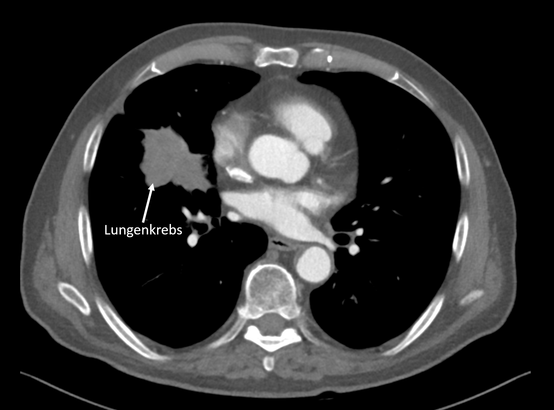

Lungen-CT

Darstellung eines Lungenkrebs im Lungen-CT (Thorax-CT) in der Radiologie Nürnberg.

Wie häufig ist Lungenkrebs?

Sowohl bei Frauen als auch bei Männern zählt Lungenkrebs zu den fünf häufigsten Krebserkrankungen. Insbesondere das Rauchen erhöht das Risiko, einen bösartigen Lungentumor zu bekommen.

Rund 85 Prozent der an Lungenkrebs erkrankten Patienten sind Raucher. Wie bei vielen Tumorarten ist auch Lungenkrebs im Frühstadium häufig symptomlos. Doch gerade in diesem Stadium ist er in der Regel heilbar. Somit ist ein frühzeitiges Erkennen wünschenswert.

Wie kann Lungenkrebs mit der Bildgebung erkannt werden?

Mithilfe einer Lungen-CT kann die Lunge millimetergenau untersucht werden. Die Untersuchung ist dabei vollkommen schmerzfrei und kann zur Beurteilung der Lunge auch ohne die zusätzliche Gabe von Kontrastmittel (nativ) erfolgen. Dabei dauert die eigentliche Bilderzeugung nur wenige Sekunden.

Wie hoch ist die Strahlendosis beim Lungen-CT?

Aufgrund der technischen Weiterentwicklung kann die Untersuchung mit Hilfe von High-End Dual-Source CT-Scannern auch mit sehr geringer Strahlenbelastung durchgeführt werden. Diese liegt unter der natürlichen Strahlenbelastung, der jeder von uns in Deutschland im Durchschnitt in einem Jahr ausgesetzt ist.